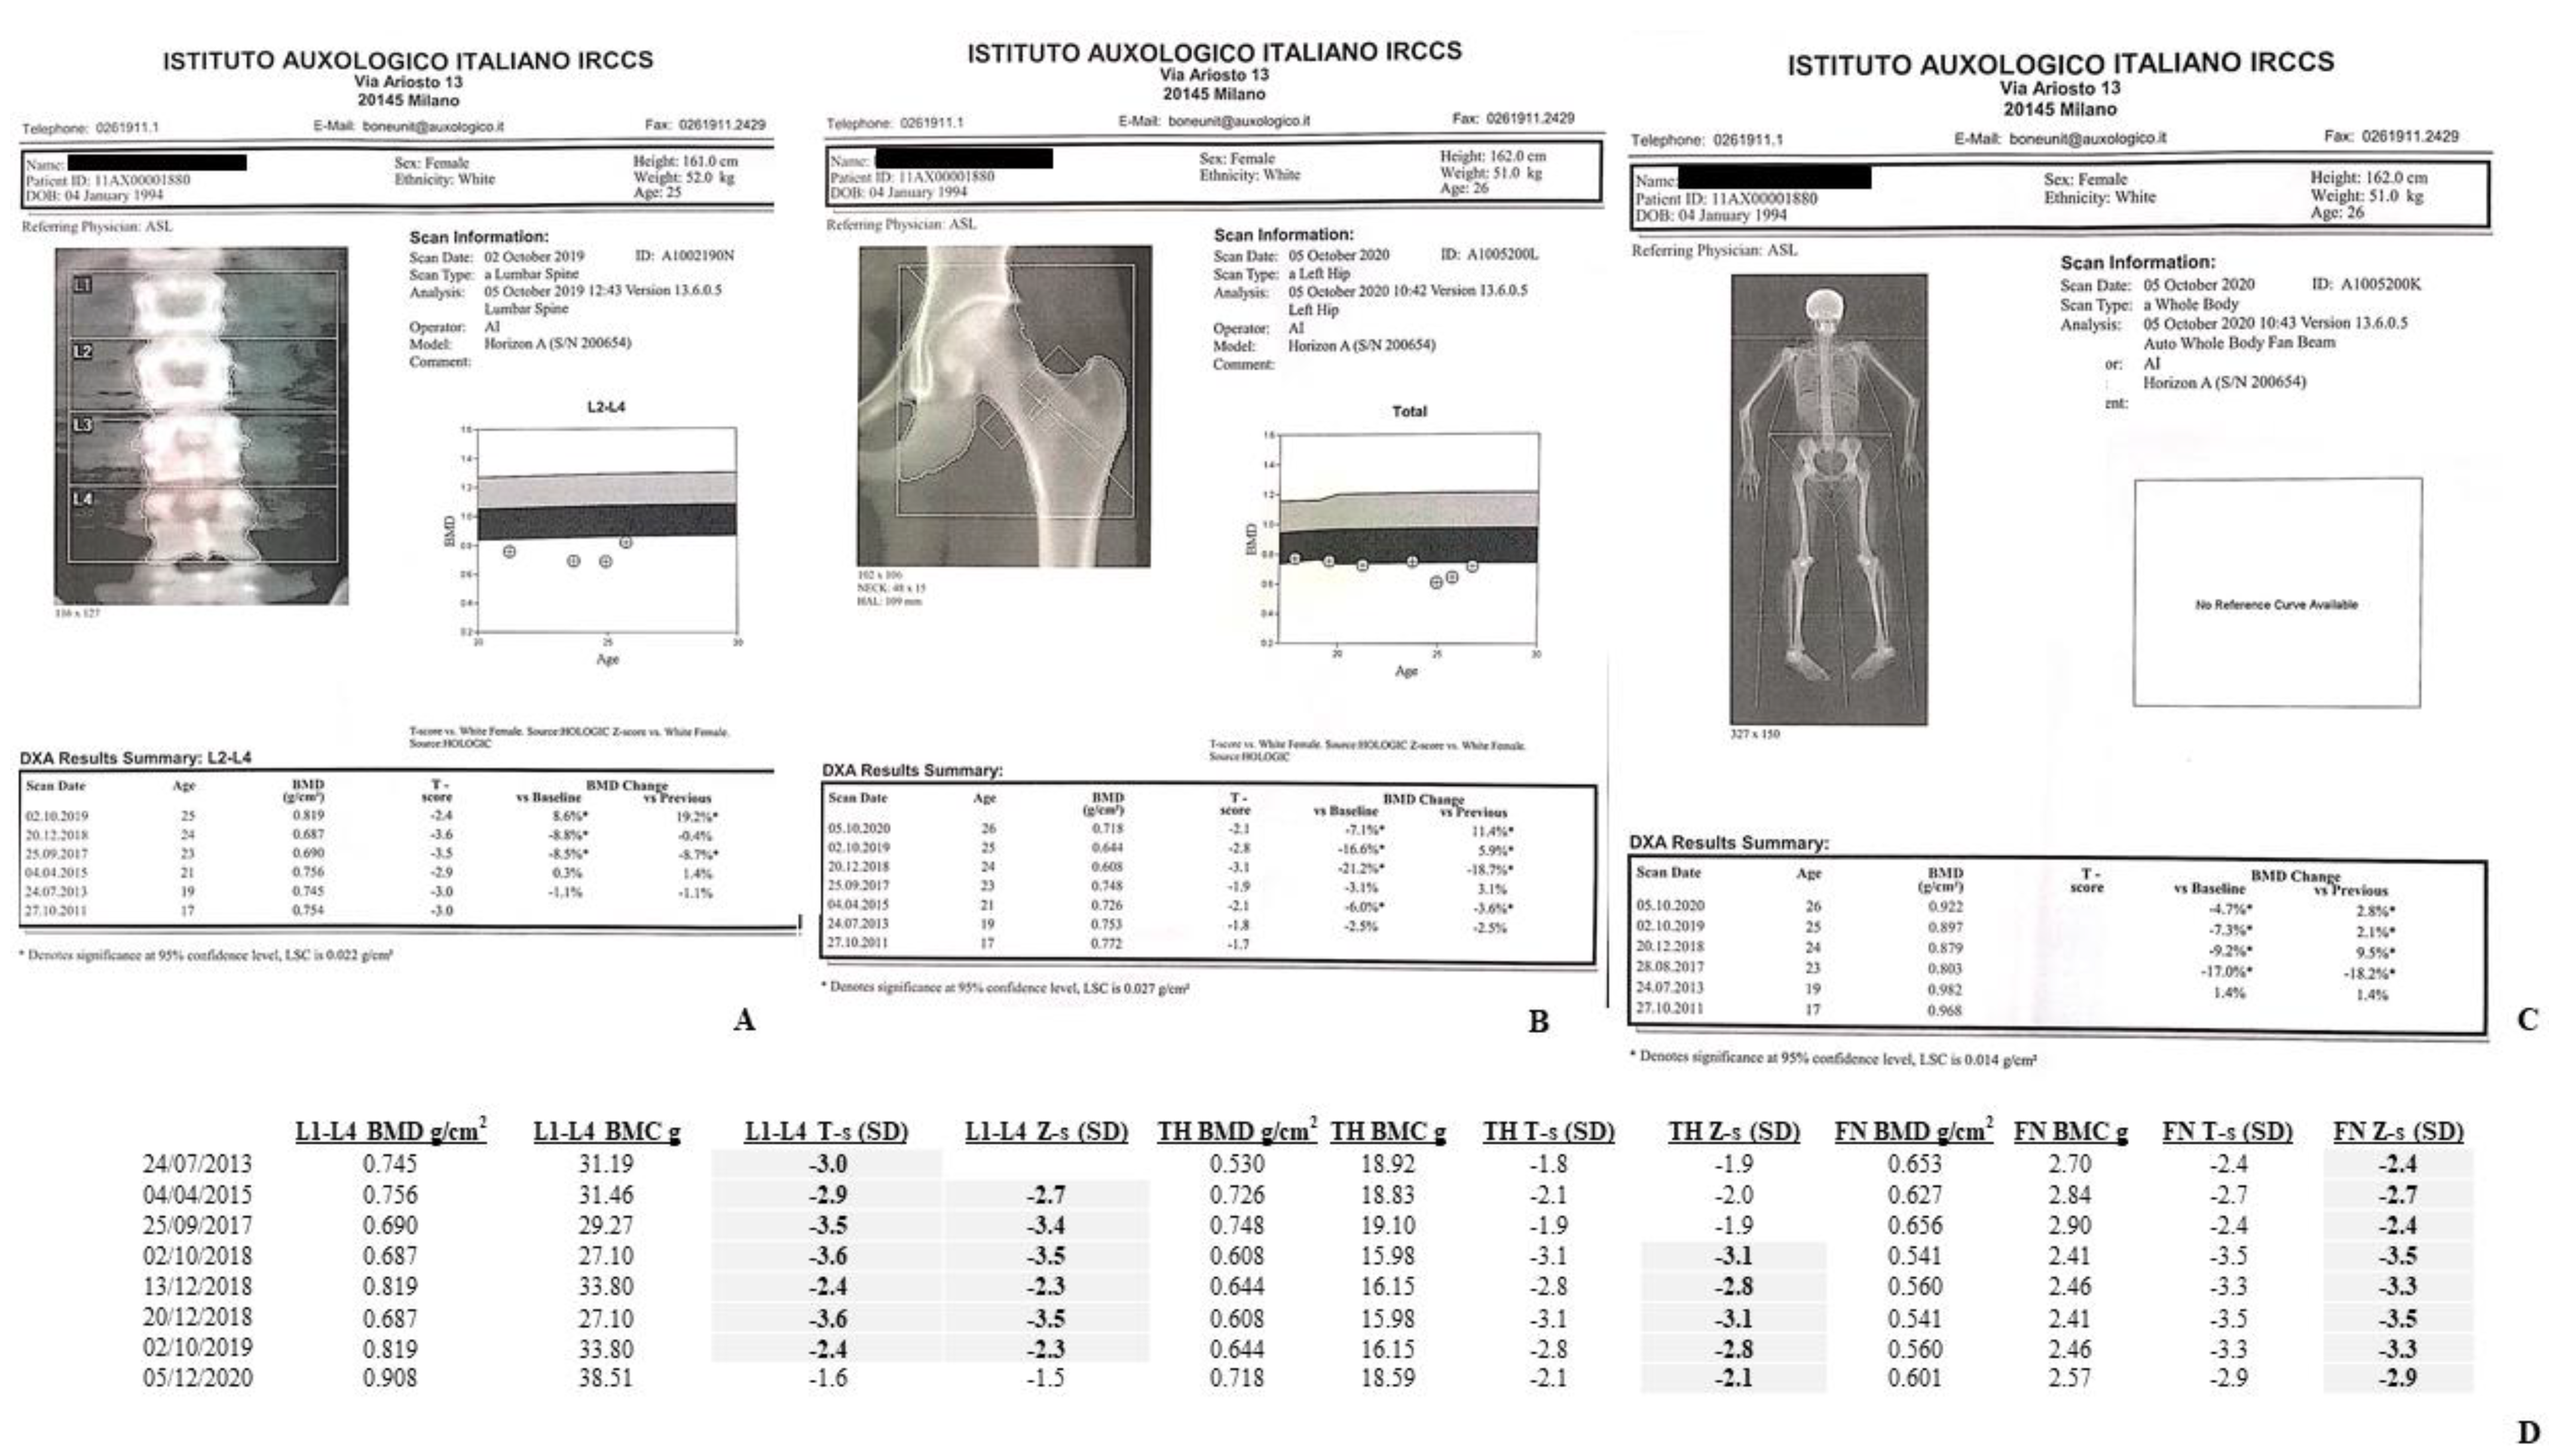

4.1. DXA Scans

4.1.1. II-1 Tw1

4.1.2. II-2 Tw2